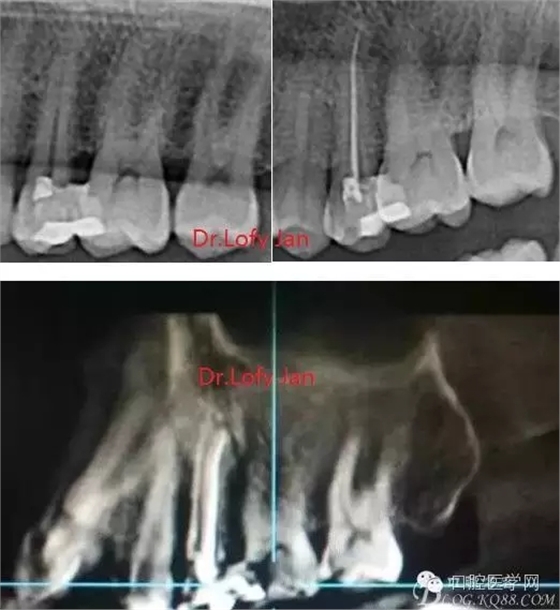

曲面斷層片在未試尖根管治療中的病例整理

前言:自己做的一些曲面斷層片在未試尖根管治療中的病例整理,發(fā)現(xiàn)問題很多包括自身的,技術(shù)的,還有設(shè)備的問題,予以總結(jié)整理并期待進(jìn)一步提高。

根管治療術(shù)是牙體牙髓疾病治療中最復(fù)雜和最關(guān)鍵的治療項(xiàng)目。根管充填材料抵達(dá)根尖、并能嚴(yán)密堵塞根尖孔,是確保根管治療效果的關(guān)鍵指標(biāo)。為了保證根管充填到位,醫(yī)生需要在術(shù)前照牙片以了解牙根根管的數(shù)量、彎曲程度和長(zhǎng)度,在術(shù)中有時(shí)需要插針照牙片來精確測(cè)量根管長(zhǎng)度,術(shù)后必須照牙片以確定是否根管充填到位,如果欠填或超填,就需要重新充填、重新照牙片確認(rèn),直到根管充填到位。所以,在患者接受根管治療時(shí)有時(shí)會(huì)反復(fù)照牙片。

《數(shù)字化根尖片、曲面斷層片、CBCT測(cè)量牙齒長(zhǎng)度準(zhǔn)確性的比較研究》文中顯示:平行投照數(shù)字化根尖片影像長(zhǎng)度和牙齒實(shí)際長(zhǎng)度之間無顯著性差異(P0.05);數(shù)字化曲面斷層片影像長(zhǎng)度和牙齒實(shí)際長(zhǎng)度之間有顯著性差異(P0.05),平均失真率為17.05%。CBCT冠狀面測(cè)量結(jié)果中除上頜前磨牙區(qū)、下頜前磨牙區(qū)與真實(shí)長(zhǎng)度差異無統(tǒng)計(jì)學(xué)意義(P0.05)外,其余6個(gè)分區(qū)差異均有統(tǒng)計(jì)學(xué)意義(P0.05);矢狀面測(cè)量結(jié)果中上頜磨牙區(qū)、下頜磨牙區(qū)、下頜前磨牙區(qū)、下頜尖牙區(qū)、下頜前牙區(qū)與真實(shí)長(zhǎng)度比較差異均有統(tǒng)計(jì)學(xué)意義(P0.05)。結(jié)論平行投照數(shù)字化根尖片較曲面斷層片和CBCT能更加精確地反映牙齒的真實(shí)長(zhǎng)度。

病例分析:曲面斷層片在x線輔助診斷與檢查中目前大多數(shù)文獻(xiàn)和著作都建議只能作為初診拍片檢查手段,不能作為終末疾病的確診與手術(shù)療效的評(píng)價(jià)指標(biāo),臨床大部分中小型門診都因?yàn)樵O(shè)備不齊全導(dǎo)致信息偏差很大。